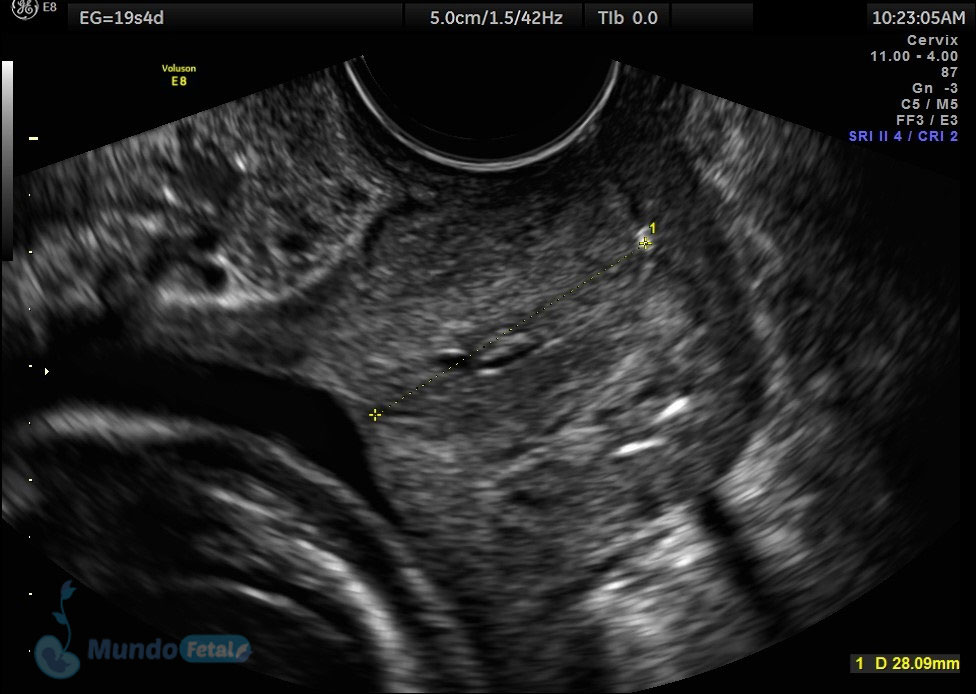

Ultrasonido 2do Trimestre 18-23 Semanas (Estructural o Anatómico)

Entre las 18 y 22 semanas, el feto ha desarrollado la mayoría de sus estructuras anatómicas, permitiéndonos valorar de manera detallada todos los órganos del bebe, descartando anomalías anatómicas fetales y datos de cromosomopatías. Prediciendo además preeclampsia (Doppler de arterias uterinas) y parto prematuro (por medio de la medición de la longitud del cérvix). En manos expertas, la detección de anomalías anatómicas supera el 80%.

LONGITUD-CERVICAL1